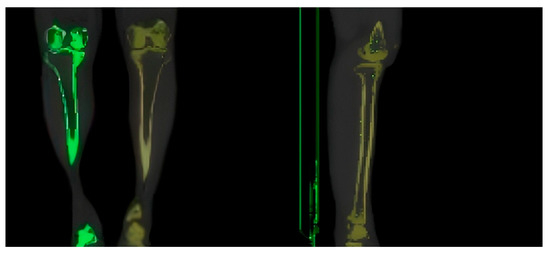

2.1. Construction of 3D Model of Human Tibia

2.2. Construction of Finite Element Model of Human Tibia